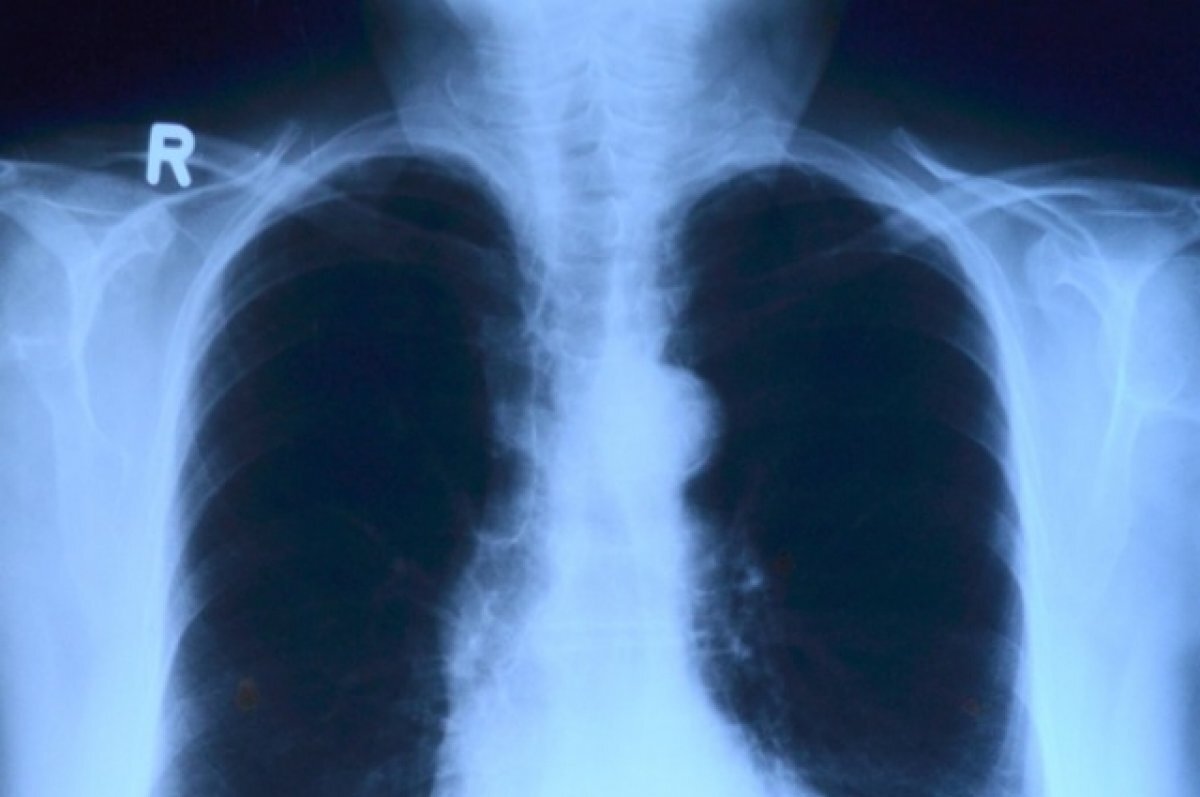

Коронавирусная инфекция влияет на кости и суставы, пишет «КП-Томск».

Воспаление, которое вызвано коронавирусом влияет и на опорно-двигательный аппарат, может вызвать мышечную слабость, а также поражение костей и суставов.